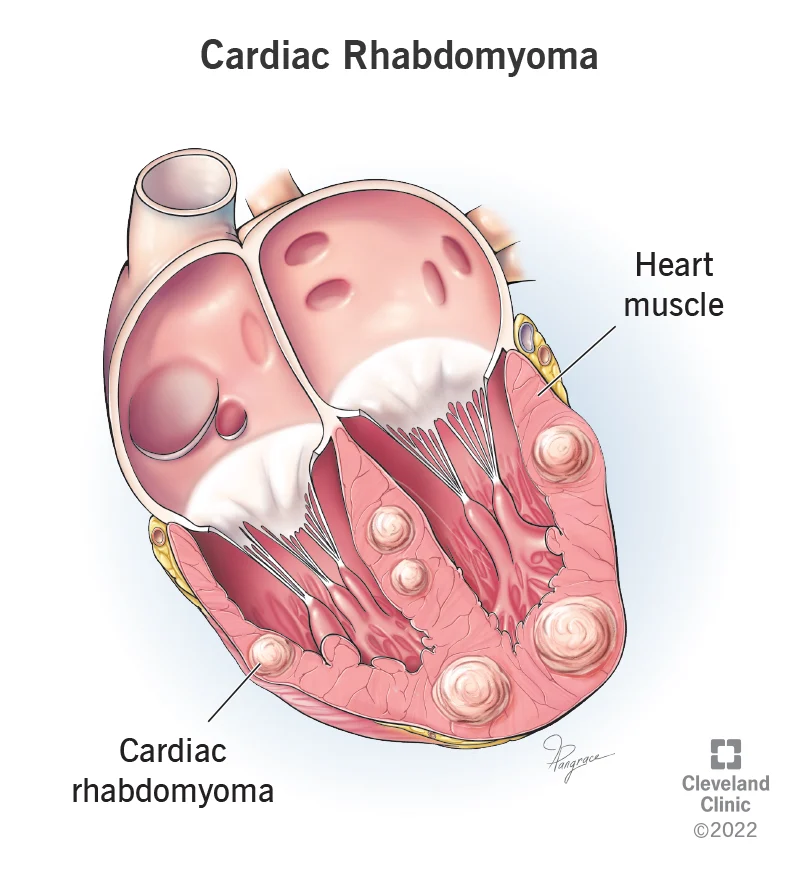

6. Heart Cancer (Primary Cardiac Tumor)

- Number of People Afflicted Yearly: total number unknown (many hospitals report treating between 1 to 2 patients each year)

- Area of Body Affected: Heart

- Is it Treatable?: Yes

- Survival Rate: 5-year survival rate after surgery is about 17%

Leading hospitals all over the world only report one or two cases of heart cancer, also known as primary cardiac tumors, each year.

This makes heart cancer one of the rarest types of the disease. Due to the fact that the cells in our hearts do not divide in the same way that cells in other regions of our bodies do, malignant and benign tumors of the heart are rather uncommon.

Since the cells that make up the heart do not divide, it is exceedingly unlikely that cancer will ever take hold in this organ. Cell division is one of the factors that contribute to the development of cancer.

Primary cardiac tumors make up only around 0.3–0.7% of the total cardiac tumor population, as determined by reports from surgical procedures and autopsies.

Only approximately a quarter of these primary cardiac tumors are malignant, and of those that are, around three-quarters are sarcomas. In addition, research has indicated that people in their 20s and 30s are most likely to be diagnosed with heart cancer.